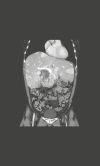

Data synthesis: To pinpoint metastatic potential in PPGLs is difficult, but nevertheless crucial for the individual patient to receive tailor-made follow-up and adjuvant treatment following primary surgery. A combination of histological workup and molecular predictive markers can possibly aid the clinicians in this aspect. Most patients with PPGLs have localized disease and may be cured by surgery. Plasma metanephrines are the main biochemical tests. Genetic testing is important, both for counseling and prognostic estimation. Apart from computed tomography and magnetic resonance imaging, molecular imaging using 68Ga-DOTATOC/DOTATATE should be performed. 123I-MIBG scintigraphy may be performed to determine whether 131I-MIBG therapy is a possible option. As first-line treatment in patients with metastatic disease, 177Lu-DOTATATE or 131I-MIBG is recommended, depending on which shows best expression. In patients with very low proliferative activity, watch-and-wait or primary treatment with long-acting somatostatin analogues may be considered. As second-line treatment, or first-line in patients with high proliferative rate, chemotherapy with temozolomide or cyclophosphamide + vincristine + dacarbazine is the therapy of choice. Other therapies, including sunitinib, cabozantinib, everolimus, and PD-1/PDL-1 inhibitors, have shown modest effect.